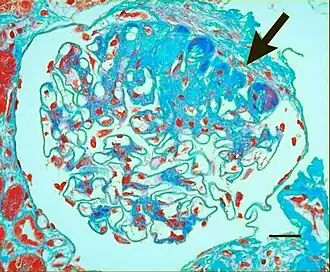

In benign nephrosclerosis, the changes occurring are gradual and progressive, however, there can be sufficient kidney reserve capacity to maintain adequate kidney function for many years.[10] The large renal arteries exhibit intimal thickening, medial hypertrophy, duplication of the elastic layer. The changes in small arterioles include hyaline arteriolosclerosis (deposition of hyaline, collagenous material), which causes glomerular collapse (wrinkling and thickening of capillary basement membranes and collapse of capillary lumen) and solidification (glomeruli exhibit sclerosis and increase in mesangial matrix). The degree of scarring correlates with the degree of glomerular filtration deficit.

Light micrograph showing signs of hypertensive nephropathy: interstitial fibrosis, tubular atrophy with thickened tubular basement membranes, and fibrous intimal thickening of a small artery (arrow).